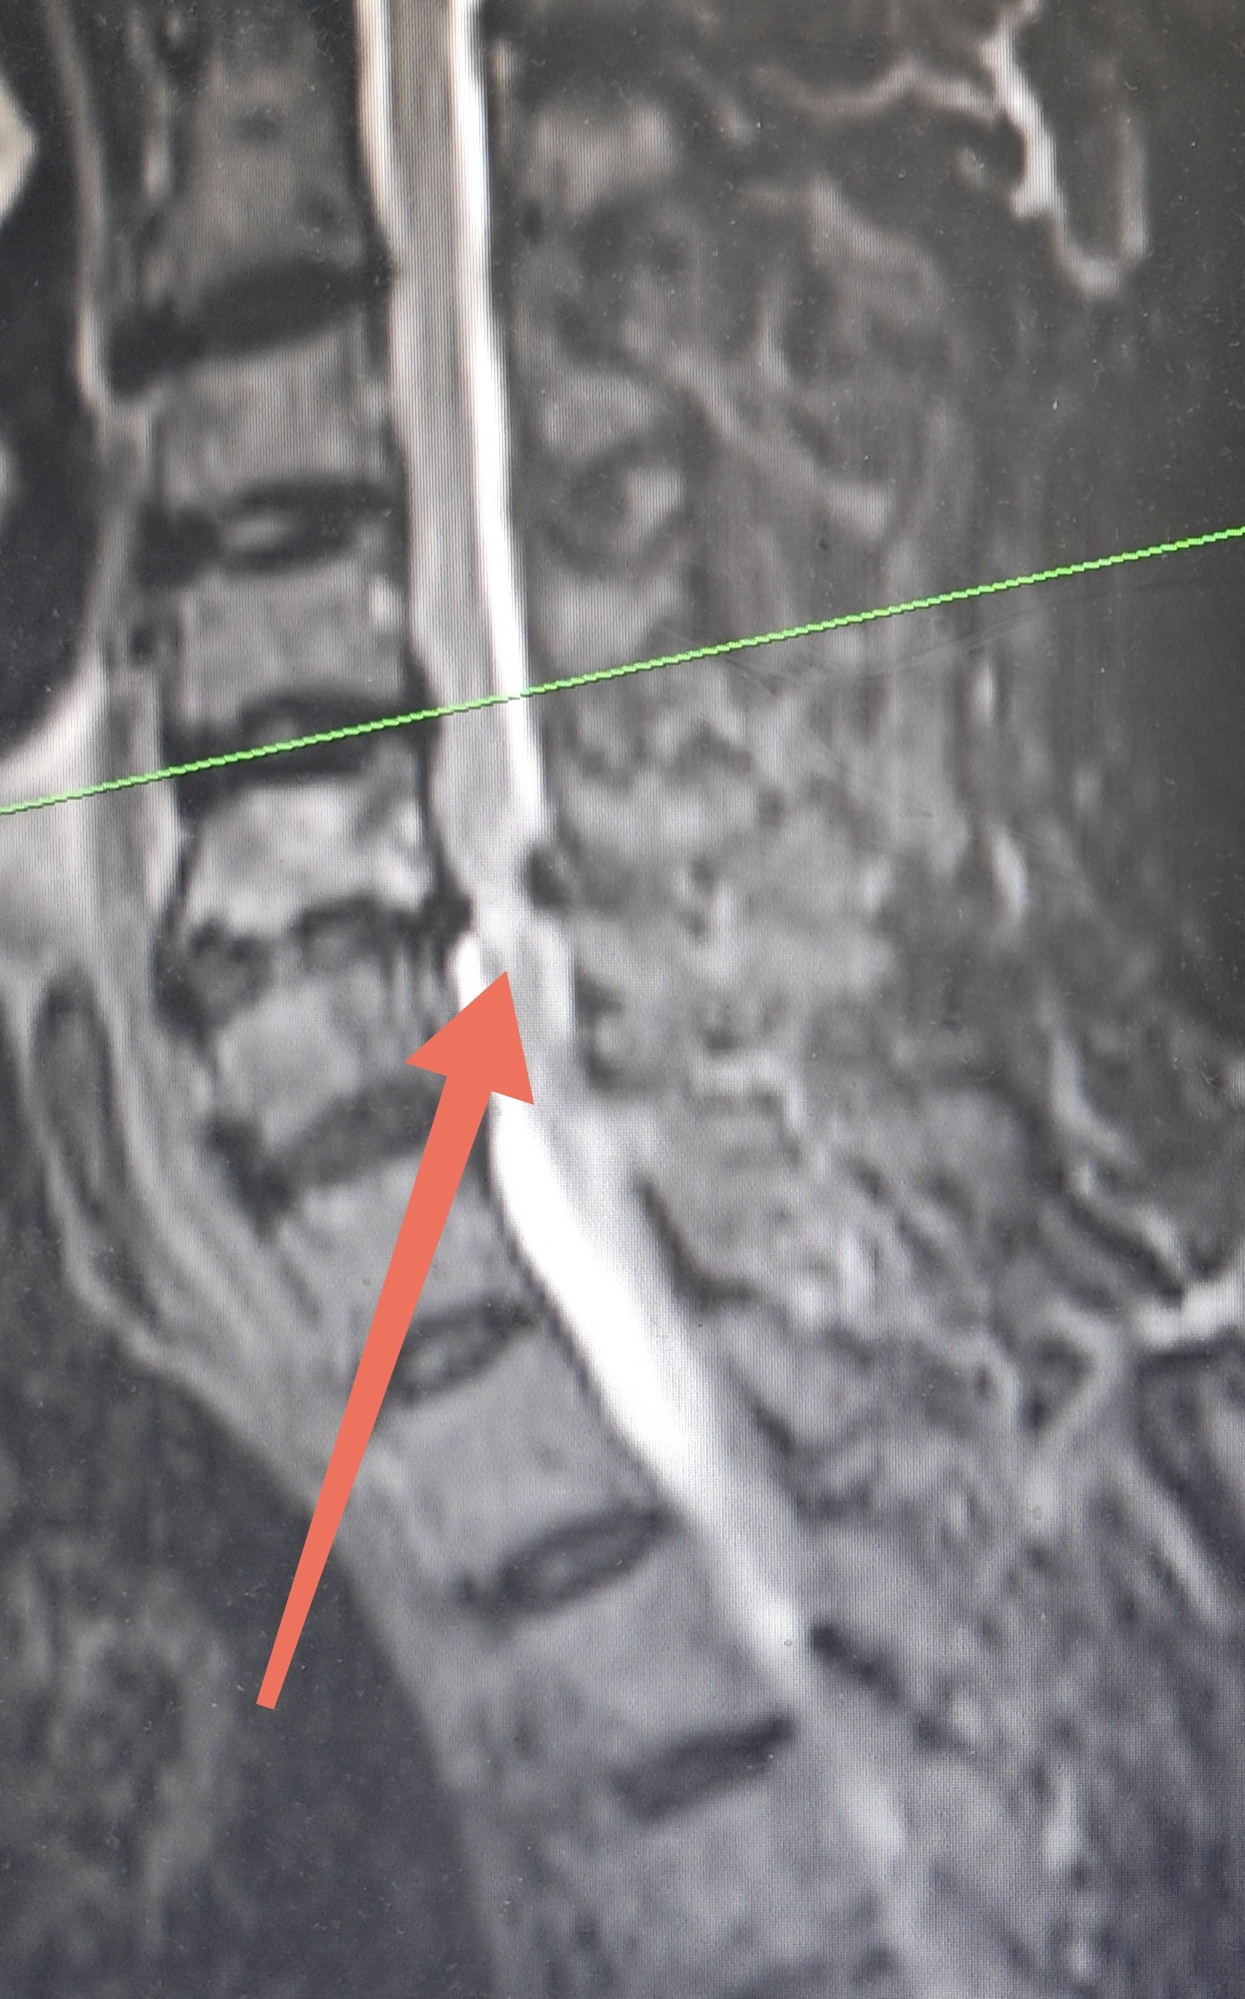

這是我們臨床上碰到的一位患者,雙下肢無(wú)力伴踩棉花感1年,頸椎MRI提示頸5-6節(jié)段椎間盤突出,脊髓壓迫,變性信號(hào)異常??紤]診斷為脊髓型頸椎病。頸椎病中最嚴(yán)重的類型,是由于頸椎退行性病變?nèi)缱甸g盤突出、椎體后緣骨質(zhì)增生、后縱韌帶鈣化等病變,直接壓迫脊髓或壓迫供應(yīng)脊髓的血管,導(dǎo)致脊髓功能障礙,并出現(xiàn)一系列臨床癥狀的疾病。其主要癥狀包括四肢感覺(jué)、運(yùn)動(dòng)以及大小便功能障礙等。只有徹底解除脊髓神經(jīng)壓迫,才會(huì)有神經(jīng)恢復(fù)的條件和可能。但神經(jīng)損傷一旦出現(xiàn),一般很難恢復(fù),壓迫時(shí)間越長(zhǎng),壓迫程度越厲害,治療獲手術(shù)的效果越差??梢哉f(shuō)如圖中這么嚴(yán)重的病情,簡(jiǎn)直就是日常生活中的定時(shí)炸彈避免頸部劇烈活動(dòng)、急剎車、跌倒外傷等,否則極有可能發(fā)生神經(jīng)功能損害加重、大小便失禁甚至癱瘓可能!希望大家都能重視起來(lái)!#脊髓型頸椎病#脊柱退行性變#醫(yī)學(xué)科普